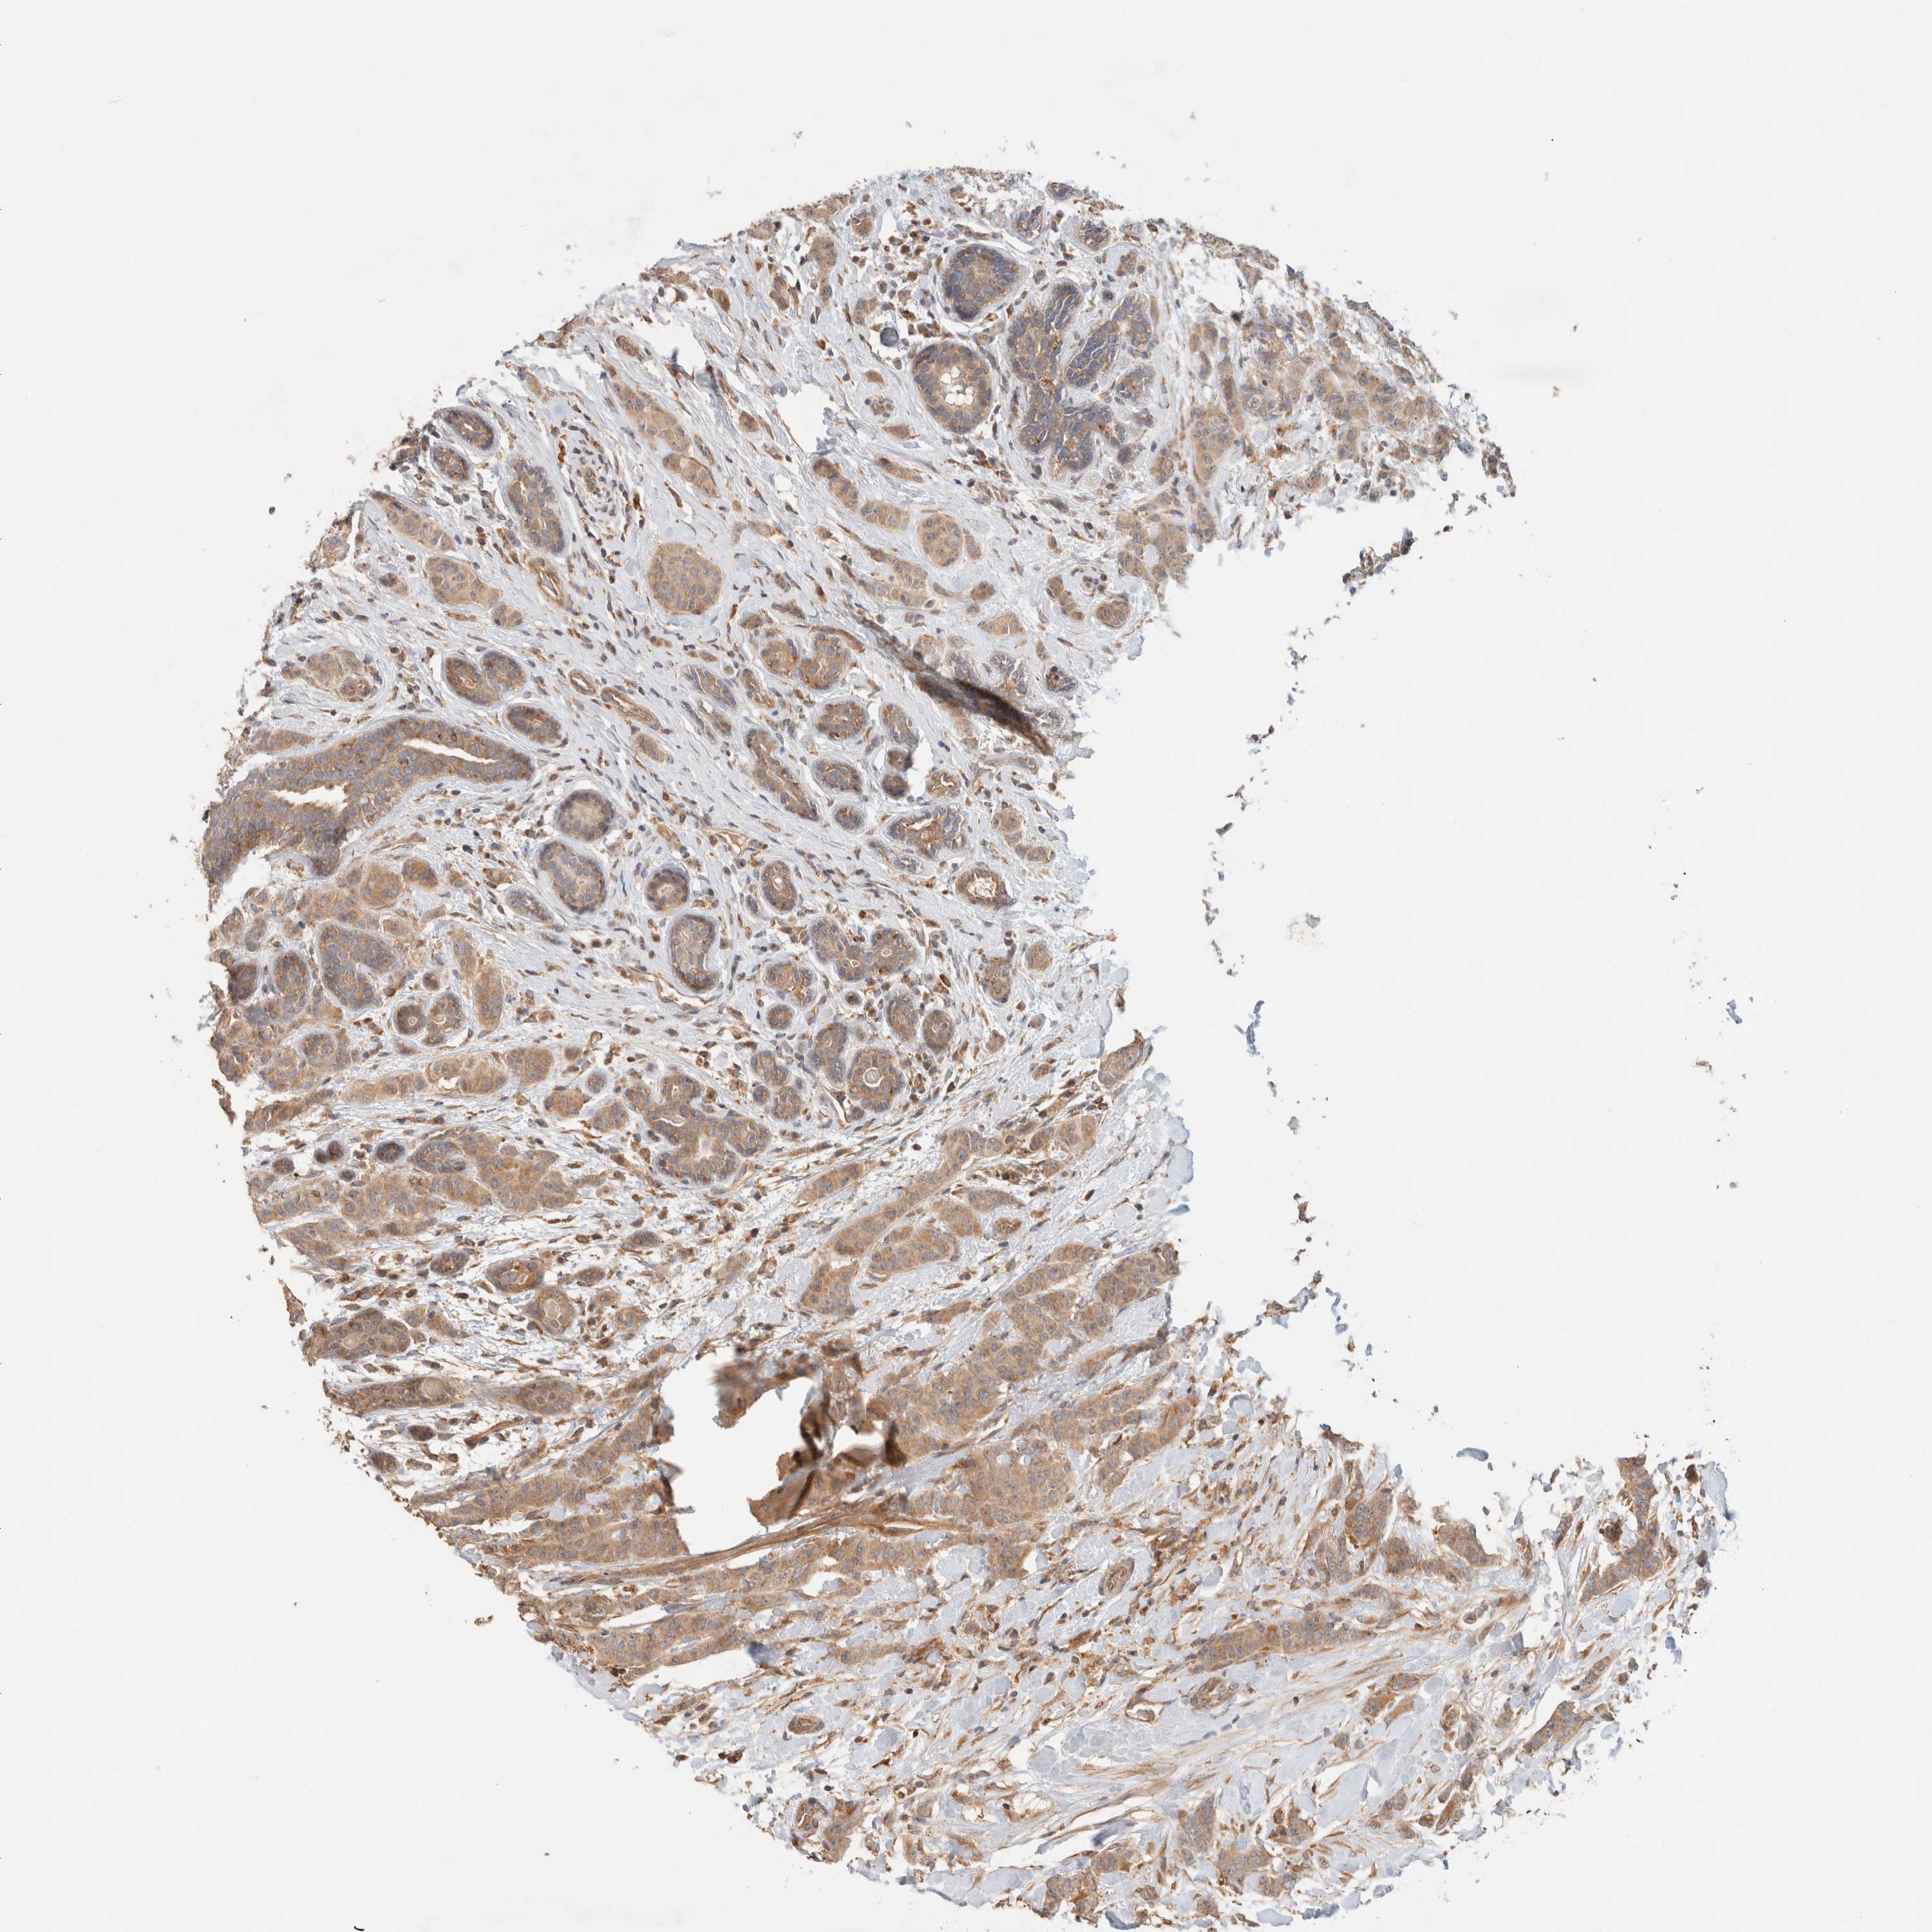

CANCER BREAST CANCER Show tissue menu

BRCA TCGA BRCA VALIDATION PROTEIN EXPRESSION

ANTIBODIES

AND

VALIDATION